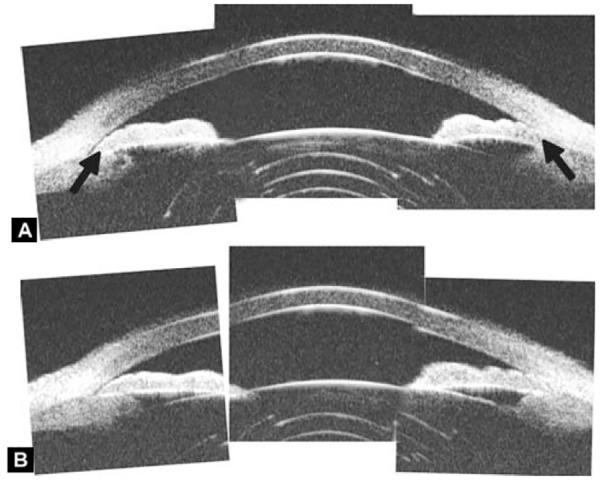

Ultrasound biomicroscopy (UBM) is a high-resolution ultrasound technique that allows noninvasive imaging of structural details of the anterior ocular segment at near light microscopic resolution and provides detailed assessment of anterior segment structures, including those obscured by normal anatomic and pathologic relations. This review gives an overview regarding the instrument, technique and its applications.

超声生物显微镜(UBM)是一种高分辨率超声技术,它能够以接近光学显微镜的分辨率对眼前节结构细节进行无创成像,并对眼前节结构进行详细评估,包括那些被正常解剖和病理关系所掩盖的结构。本文综述了该仪器、技术及其应用。